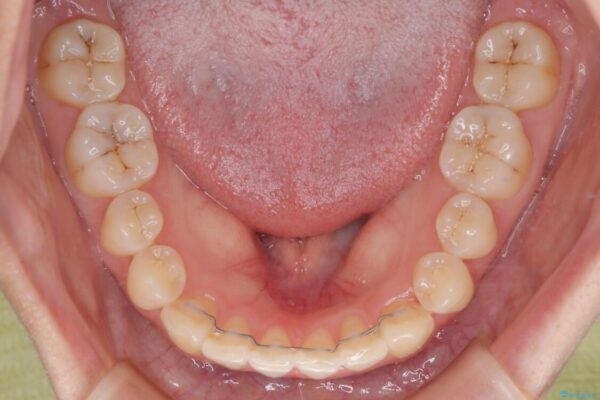

診察の結果、上下の前歯部に**叢生(そうせい/歯のガタガタ・重なり)**が認められました。

特に上の前歯にはねじれや重なりがあり、審美的にも清掃性にも影響している状態でした。

治療前

• 前歯のねじれ・ガタガタを10か月で改善!20代女性の矯正治療|クリアブラケットでむし歯になりにくい歯並びへ改善 治療前画像